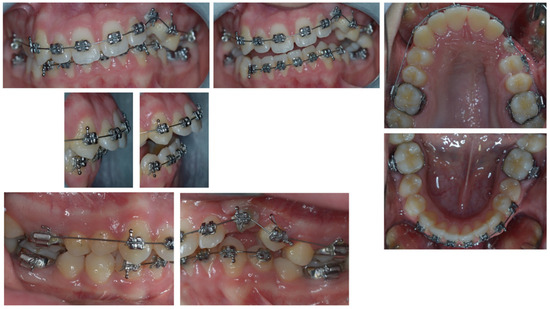

3. Therapeutic Interventions

4. Follow-Up and Outcomes